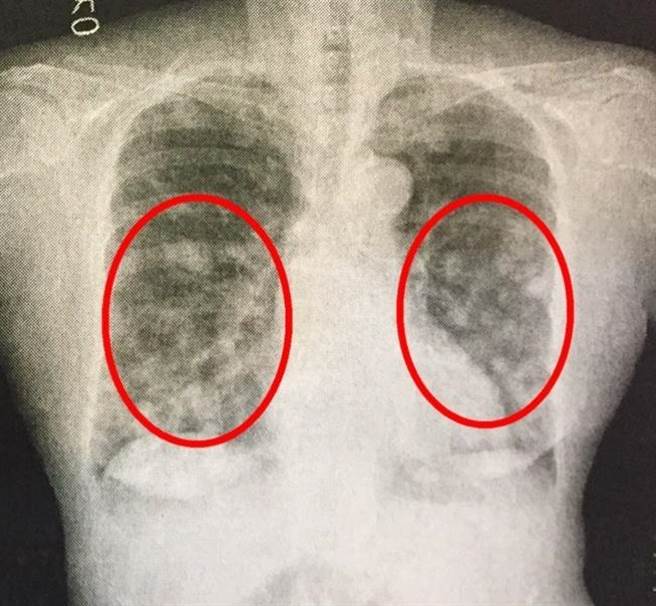

非霍奇金淋巴瘤影像-医学影像图,_医学图库